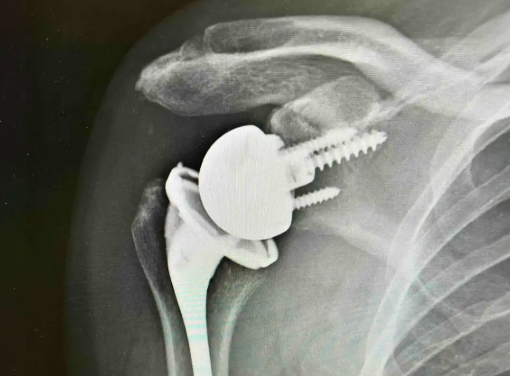

드물게 견봉 성형술, 인공관절 치환술(파열정도가 심해 봉합이 어렵거나 관절염이 동반된경우) 등이 필요할 수도 있습니다.

Reverse shoulder replacement